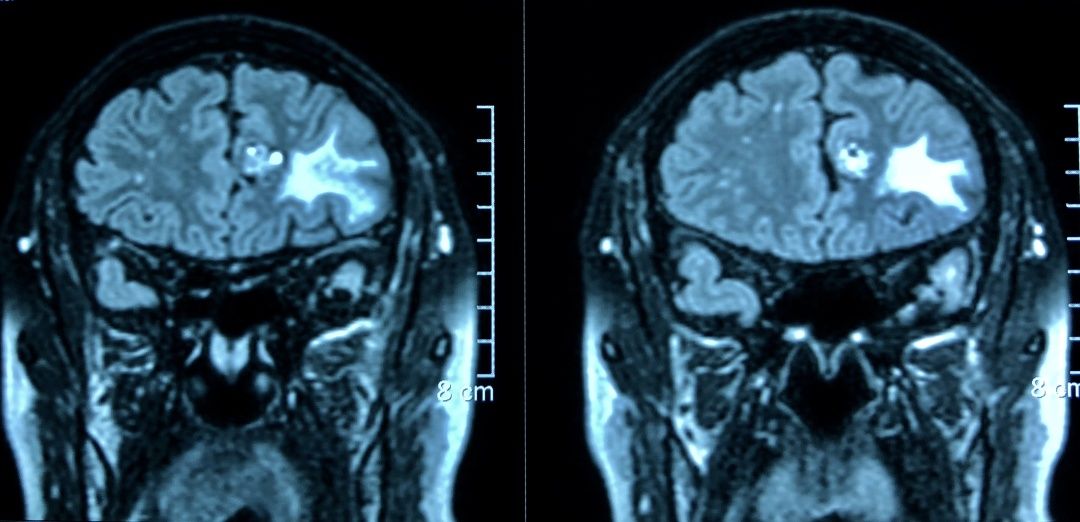

头颅MRI增强显示:左侧额叶中线旁爆米花样混杂信号肿块,双侧额叶、颞叶软化灶伴胶质增生。脑电图显示:左额有癫痫样放电。

结合CT、MRI增强、脑电图检查结果,诊断为:左侧额叶海绵状血管瘤,左额叶软化灶,患者之前的头晕、头痛症状就是因此引起。患者目前不仅有海绵状血管瘤,并且脑电波异常,虽然目前没有明显的癫痫样发作,但是以后严重了会出现临床症状,刘长青教授建议患者手术治疗,切除海绵状血管瘤,解除出血风险,同时去掉癫痫灶。

在与患者及家属充分沟通后,5月9日上午,由刘长青教授主刀,李云副主任医师为助手,在静吸复合麻醉下进行冠切左额颞入路左额叶海绵状血管瘤切除+软化灶切除+颅骨修补术。术后,患者恢复非常快,12天即拆线出院。